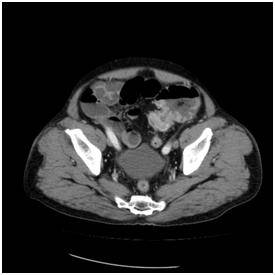

![에스자 결장에 생긴 대장암으로 장폐쇄가 생겨서 유발된 변비 [서울대병원 제공]](https://img2.daumcdn.net/thumb/R658x0.q70/?fname=https://t1.daumcdn.net/news/201905/15/yonhap/20190515070012793uxdl.jpg)

![서행성변비 복부 CT 영상. 상행 결장에서 횡행 결장이 심하게 늘어나 있으며 이보다 항문에 가까운 쪽에 대변이 차 있다. 대장 내 종괴 등 폐쇄를 유발하는 원인 병변은 보이지 않는다. [서울대병원 제공]](https://img2.daumcdn.net/thumb/R658x0.q70/?fname=https://t1.daumcdn.net/news/201905/15/yonhap/20190515070012871ycxl.jpg)